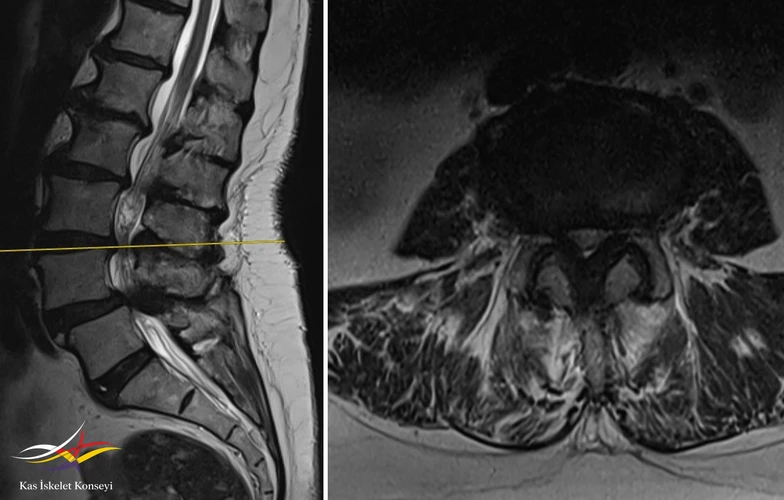

Resim 5. L4-5 seviyesinde dejeneratif listezis ve belirgin kanal darlığı görülmekte.